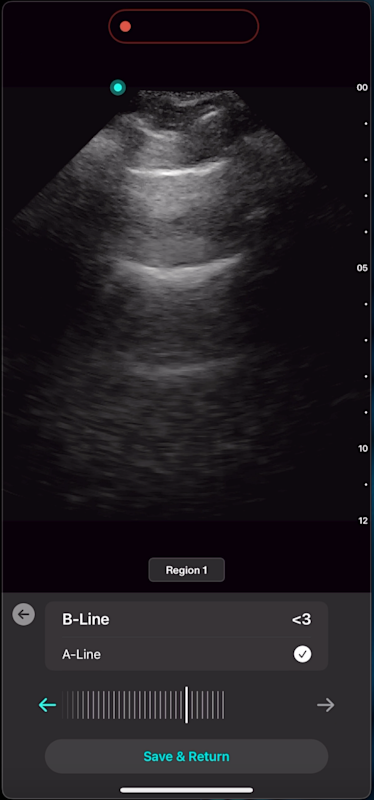

With Lung AI, you can determine the presence or absence of B-lines reliably in seconds.

Lung AI

High Reliability

Excellent agreement with B-lines done by experts (experienced echosonographers) with an Inter Class Correlation (ICC) score of 0.93

High Accuracy

AI matches or exceeds accuracy seen in expert measurements for the presence/absence of A-lines with the Cohen's Kappa Coefficient score of 0.84

High Sensitivity

Lung ultrasound has high sensitivity (94%) and specificity (92%) for counting B-lines to detect Acute Cardiogenic Pulmonary Edema (ACPE) ⁹